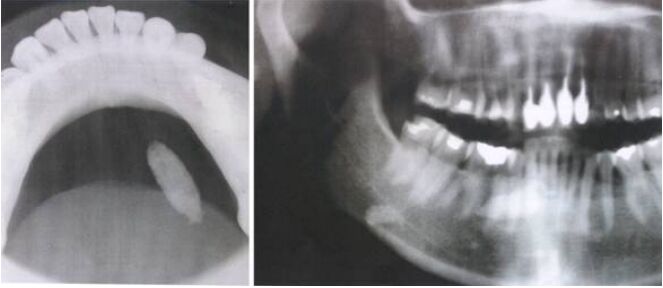

78.附圖兩張X光片所呈現的影像,其臨床診斷最可能是下列何者? (A)纖維性發育不良(fibrous dysplasia) (B)淋巴結(lymph node) (C)造釉細胞瘤(ameloblastoma) (D)涎石病(sialolithiasis)